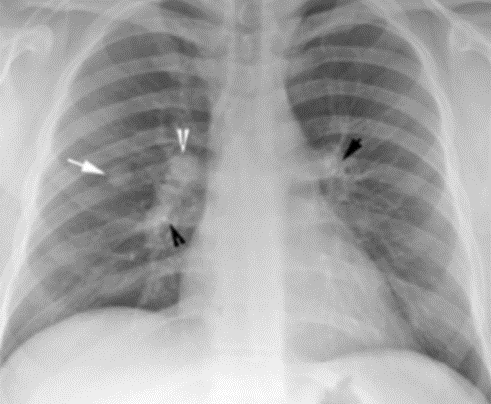

두 번째로 정기 검진입니다. 특히 흡연자나 가족력이 있는 사람 등 고위험군은 정기적인 흉부 X선 검사나 저선량 CT 검사를 통해 조기에 폐결절을 발견하는 것이 중요합니다. 정기 검진을 통해 폐결절을 조기에 발견하면 치료 효과가 높아지고, 심각한 합병증을 예방할 수 있습니다.